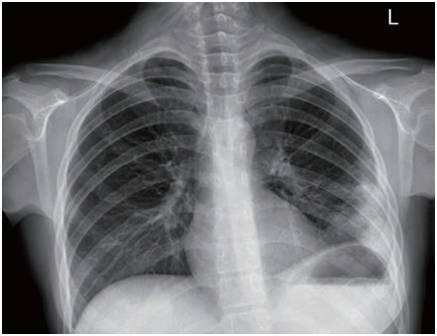

新型冠状病毒肺炎(COVID-19)自爆发以来,已成为全球关注的公共卫生问题,了解其早期症状,对于及时识别、隔离和治疗至关重要,新型肺炎在发病初期往往表现为一些轻微或非特异性症状,容易被误认为普通感冒或流感,以下是新型肺炎前几天常见的症状,帮助大家提高警惕,及早采取防护措施。

部分患者在早期可能出现轻微的呼吸急促,尤其在活动后加重,随着病情发展,呼吸困难可能变得明显,需警惕肺部感染加重的可能。